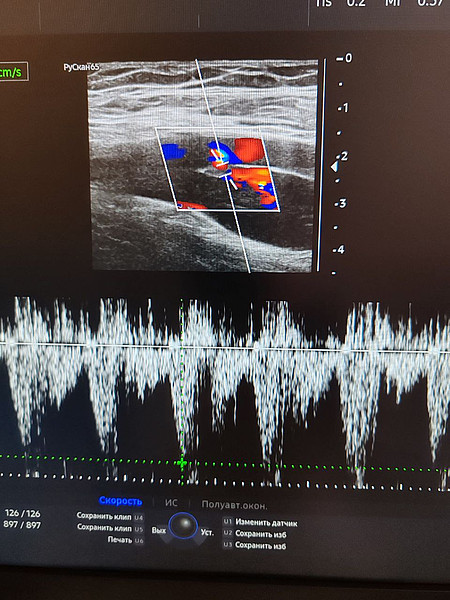

Ежегодно более 32 000 ультразвуковых исследований выполняется пациентам в поликлиниках Кировской клинической больницы №7